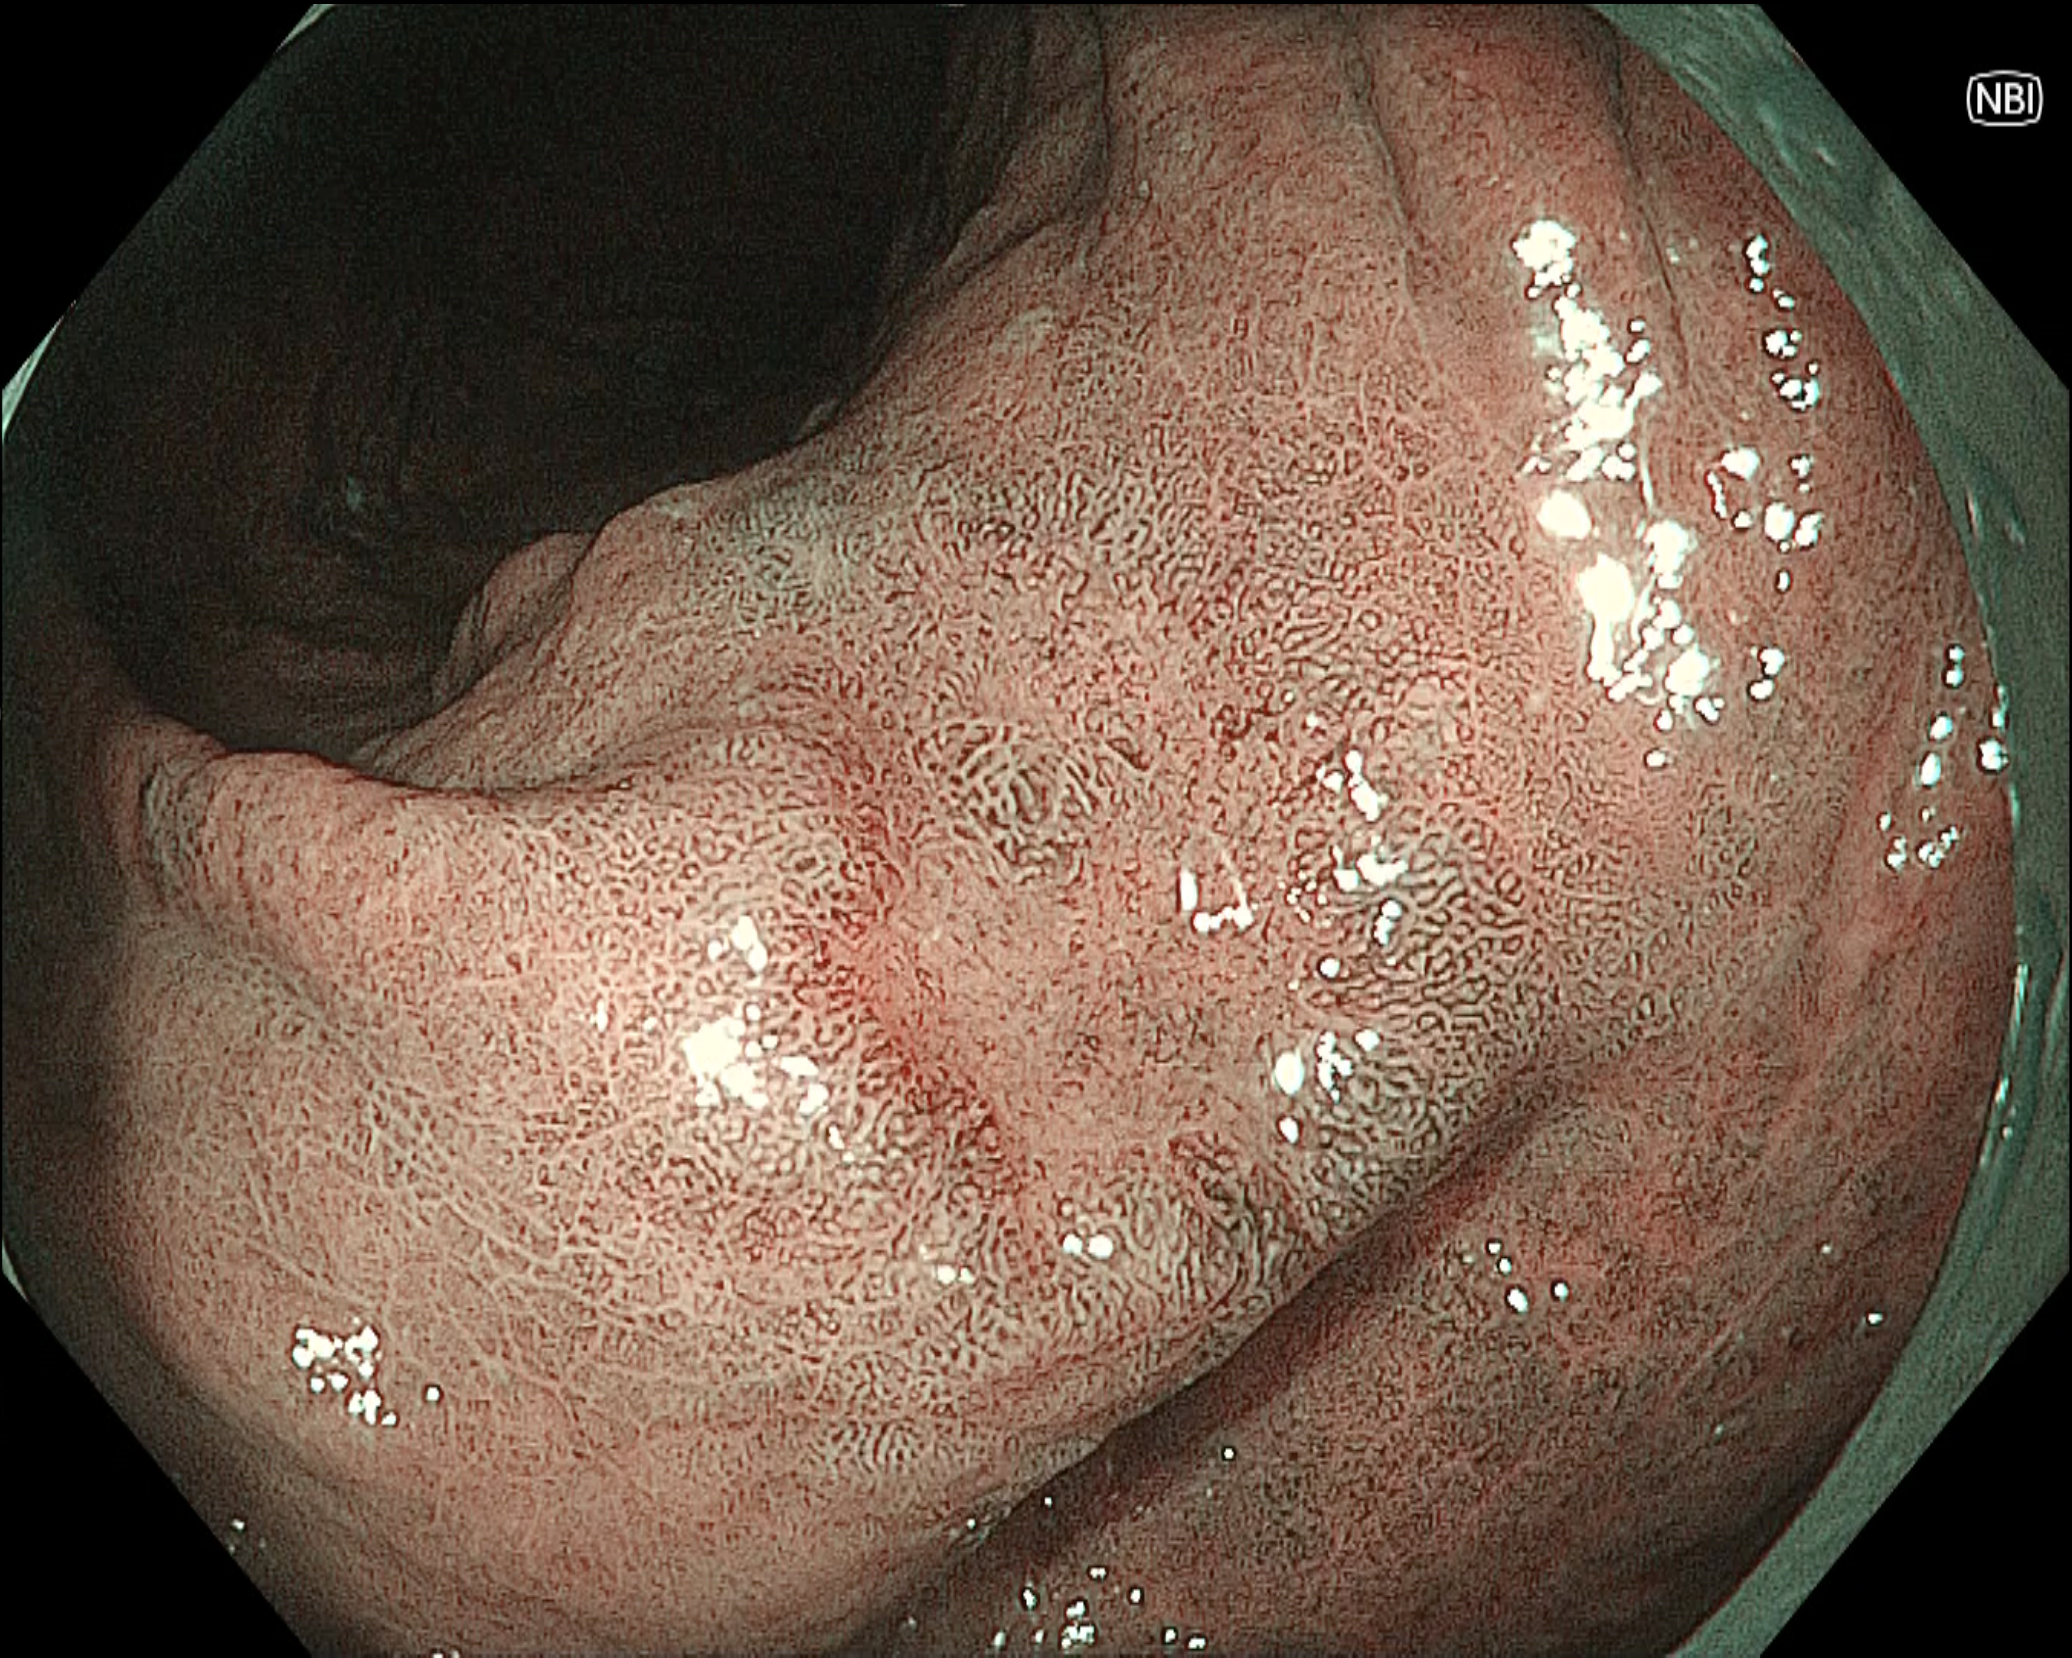

• NBI観察(中遠景)

強調設定:B8

図1

NBI観察では陥凹性病変の辺縁隆起部は褐色調を呈しており、白色光観察と比較して病変境界を視認しやすい。